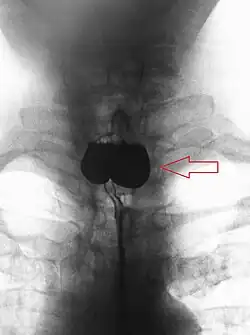

A Zenker's diverticulum, also pharyngeal pouch, is a diverticulum of the mucosa of the human pharynx, just above the cricopharyngeal muscle (i.e. above the upper sphincter of the esophagus). It is a pseudo diverticulum or false diverticulum (only involving the mucosa and submucosa of the esophageal wall, not the adventitia), also known as a pulsion diverticulum.

When there is excessive pressure within the lower pharynx, the weakest portion of the pharyngeal wall balloons out, forming a diverticulum which may reach several centimetres in diameter.

While traction and pulsion mechanisms have long been deemed the main factors promoting development of a Zenker's diverticulum, current consensus considers occlusive mechanisms to be most important: uncoordinated swallowing, impaired relaxation and spasm of the cricopharyngeus muscle lead to an increase in pressure within the distal pharynx, so that its wall herniates through the point of least resistance (known as Killian's triangle, located superior to the cricopharyngeus muscle and inferior to the thyropharyngeus muscle. Thyropharyngeus and cricopharyngeus are the superior and inferior parts of inferior constrictor muscle of pharynx respectively). The result is an outpouching of the posterior pharyngeal wall, just above the esophagus.[3]

A combination of the simple barium swallow and a thorough endoscopy will normally confirm the diverticulum.[4]